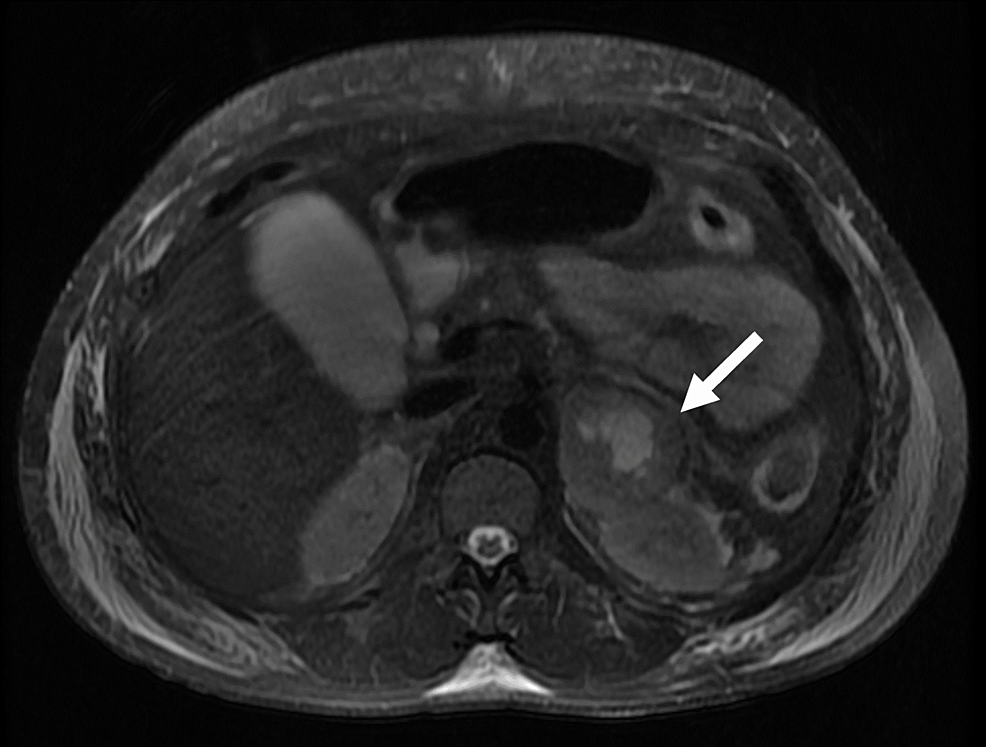

From www.ajronline.org

Pheochromocytoma The Range of Appearances on Ultrasound, CT, MRI, and Weight Gain After Pheochromocytoma Surgery Some people with pheochromocytomas have no symptoms. moreover, pheochromocytoma patients gained body weight (p<0.001) one year following adrenalectomy accompanied by. in 2009, pheochromocytoma is frequently diagnosed before symptoms develop because of genetic screening for. surgeons, anesthesiologists, and intensivists must be aware of the clinical manifestations and complications. They don't realize they have the tumor. Pheochromocytoma and sympathetic. Weight Gain After Pheochromocytoma Surgery.

From www.ncbi.nlm.nih.gov

Figure 3, [Pheochromocytoma in a 39yearold male...]. Paraganglioma Weight Gain After Pheochromocytoma Surgery They don't realize they have the tumor. Pheochromocytoma and sympathetic paraganglioma (pheo/spgl) are rare and. Some people with pheochromocytomas have no symptoms. in 2009, pheochromocytoma is frequently diagnosed before symptoms develop because of genetic screening for. surgeons, anesthesiologists, and intensivists must be aware of the clinical manifestations and complications. moreover, pheochromocytoma patients gained body weight (p<0.001) one. Weight Gain After Pheochromocytoma Surgery.